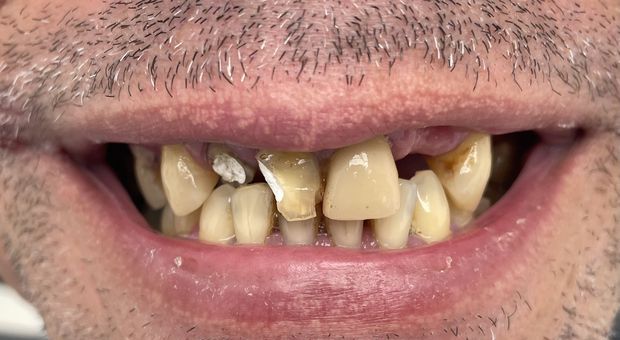

Pełna rekonstrukcja łuków zębowych, podwyższenie zgryzu, odbudowa utraconych tkanek zębów z wykonaniem koron cyrkonowych licowanych ceramiką oraz ruchomych uzupełnień protetycznych.